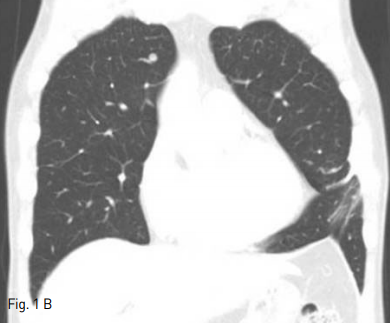

Supine position에서 시행한 cone beam CT(CBCT)상 right lung의 upper lobe에 위치하는 약 7mm 지름의 결절은 관찰가능하였다. 통증조절을 위해 Lidocaine국소 마취와 Midazolam 2mg i.v. 하였다. CBCT guide 하에 2개의 2.5cm Octopus electrode(STARmed, Kyeonggi-do, Korea)를 병변에 삽입하였으며, 이중 upper electrode가 병변을 관통한 상태였고, lower electrode는 제거하였다(Fig.2). 12분간 RF ablation을 시행하였으며, CBCT상 병변 주변으로 ground glass opacty(GGO)가 형성된 것을 확인하였다 (Fig. 3). 마지막 CBCT상 RF ablation 으로 인한 volume loss로 인하여 mediastinal pleura 가 병변쪽으로 deviation된 것이 관찰되었고, 출혈, 기흉 등의 합병증은 없었다. 시술 중 통증은 경미하였다.

Fig 3A

Axial & sagittal CBCT scan show post procedure ground glass opacity with sufficient safety margin. Mild retraction of right anterior mediastinum to the lesion may be shown. There was no evidence of pneumothorax or hemothorax.

Fig 3B